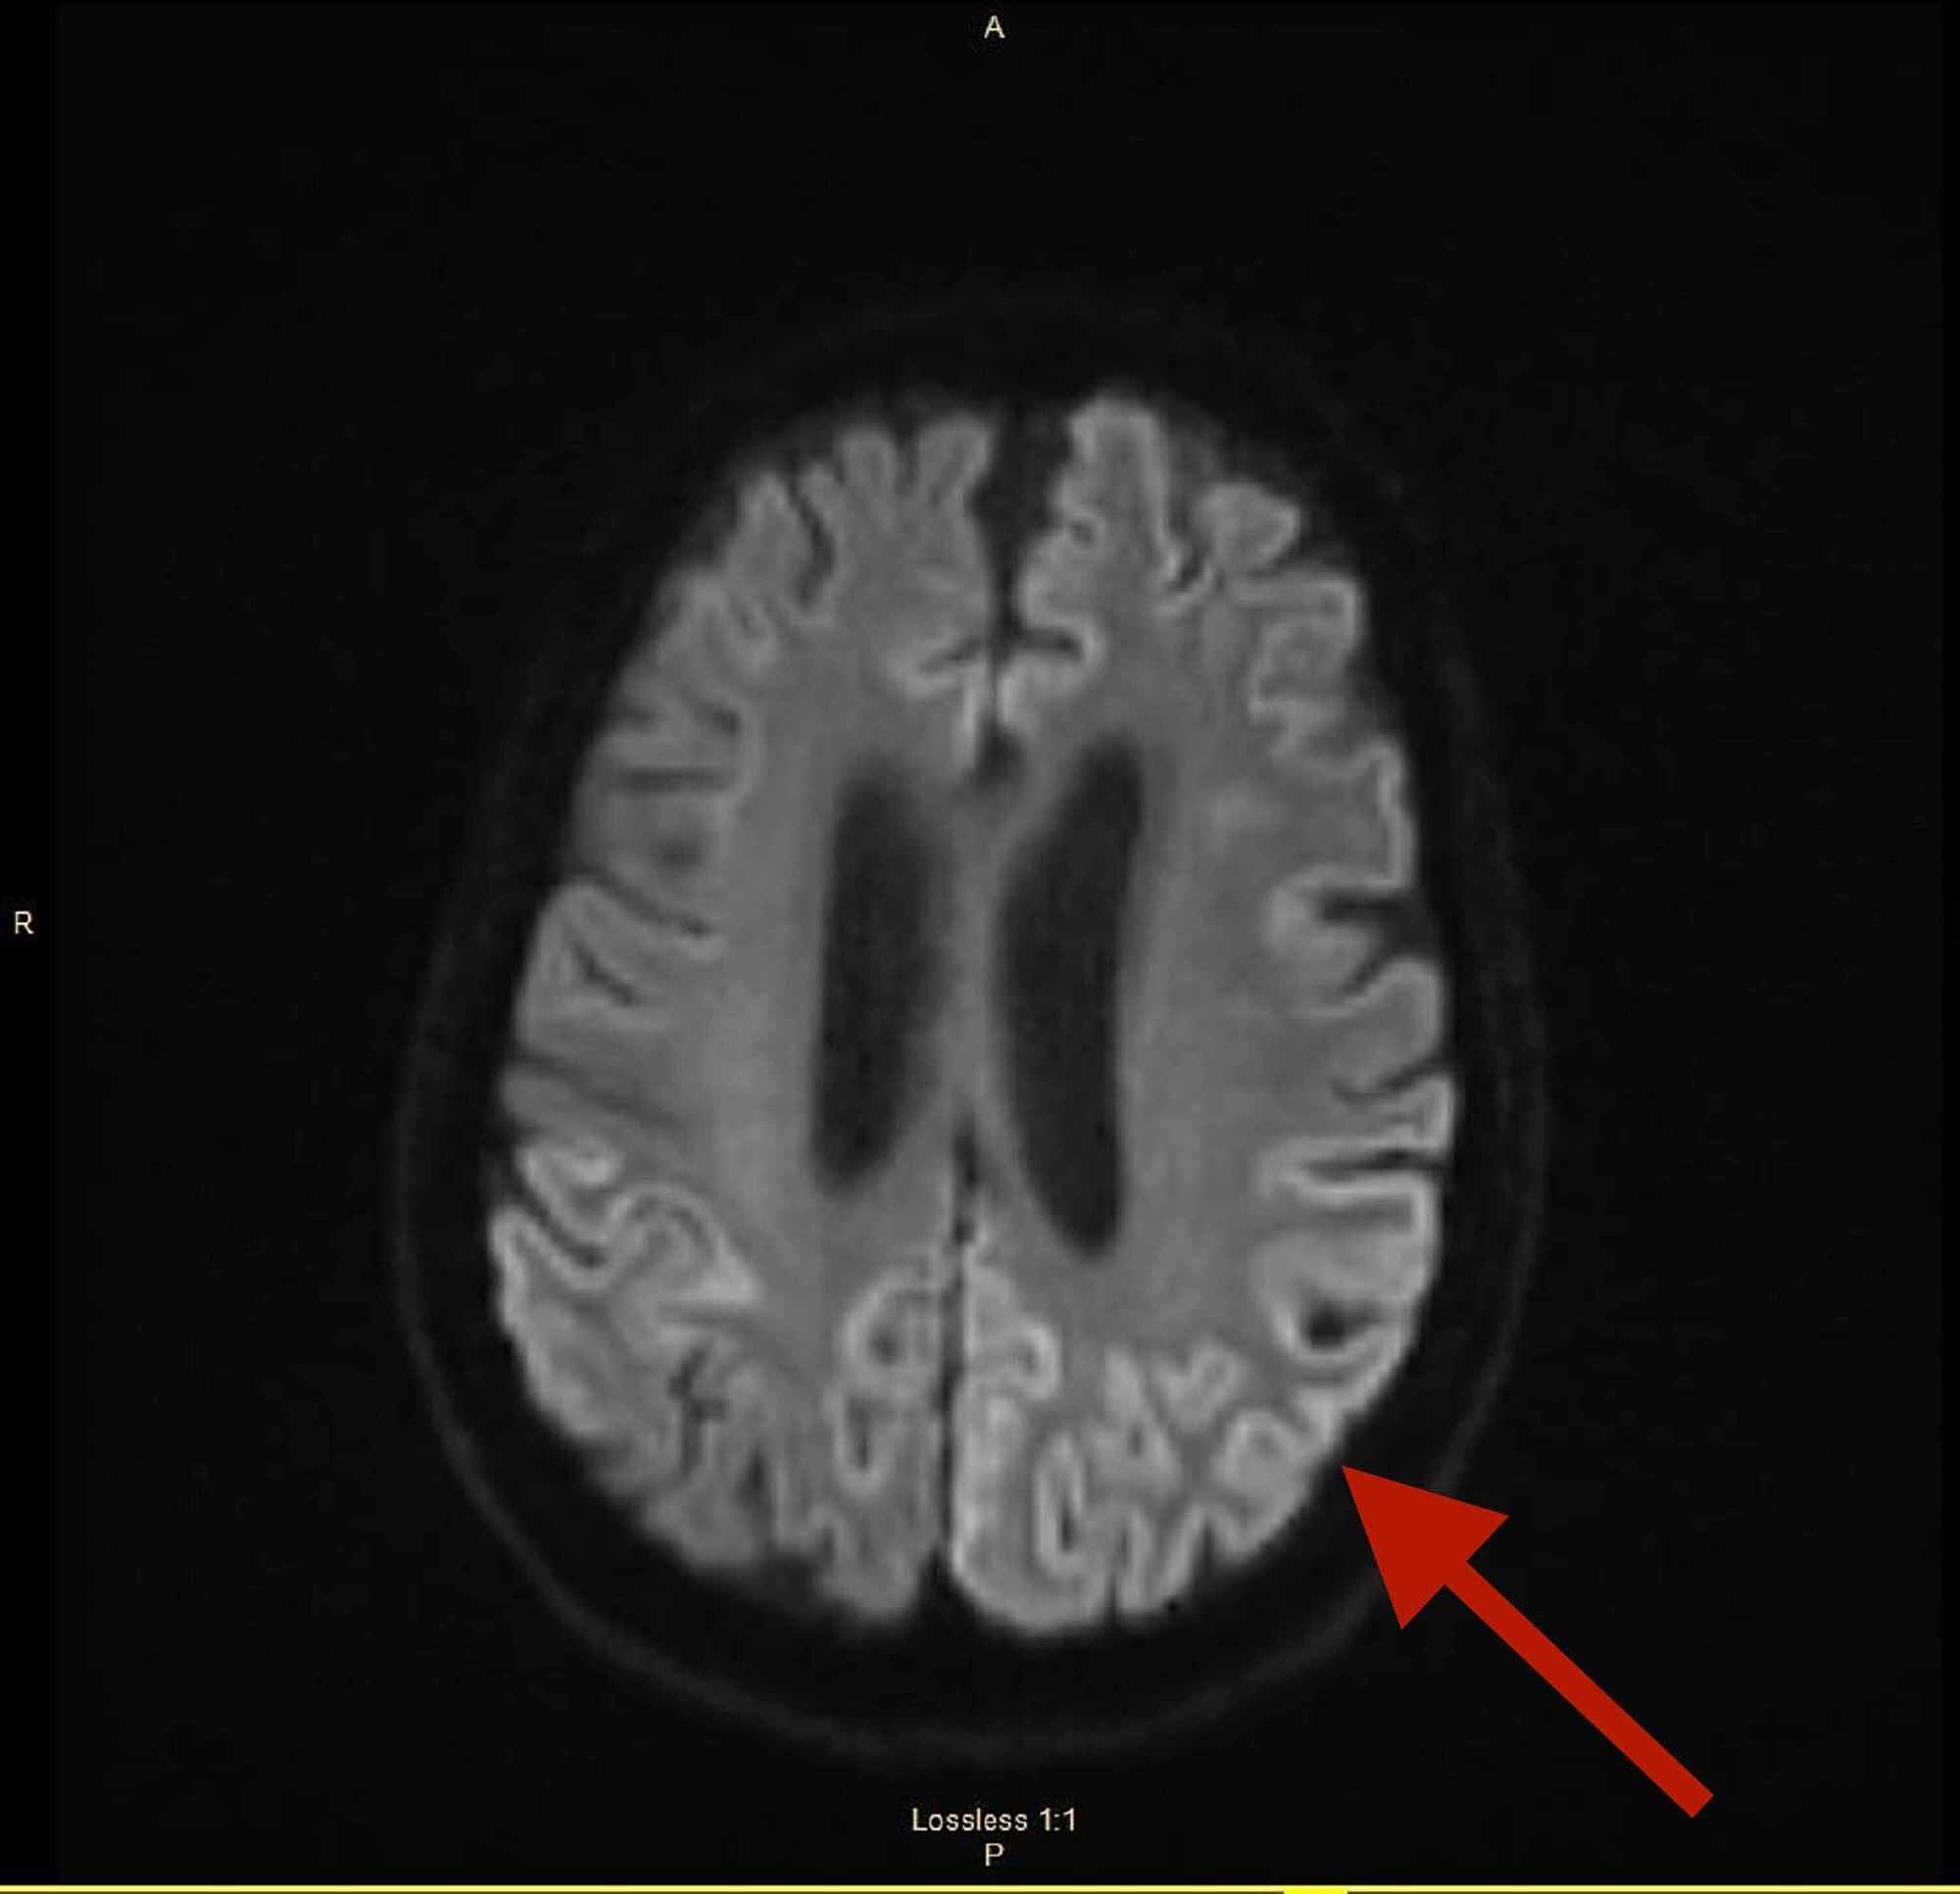

Creutzfeldt Jakob Disease Rad . The clinical syndrome, especially with the rapid cognitive deterioration, the typical mri pattern and. This condition belongs to a group of.

The clinical syndrome, especially with the rapid cognitive deterioration, the typical mri pattern and. This condition belongs to a group of.